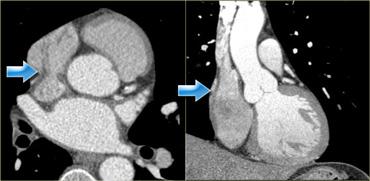

Tái tạo mặt cắt ngang (trái) và mặt cắt vành (phải) cho thấy mào tận cùng (mũi tên xanh) và vị trí của nó trong nhĩ phải

Mào tận cùng (Crista terminalis)

Trong nhĩ phải có mào tận cùng, một gờ cơ chạy từ lỗ vào của tĩnh mạch chủ trên đến lỗ vào của tĩnh mạch chủ dưới.

Cấu trúc này phân tách phần nhẵn của nhĩ phải – xoang tĩnh mạch – với tiểu nhĩ phải có cấu trúc bè cơ.

Trên các hình ảnh bên trái, nó hiện diện như một cấu trúc tuyến tính nhẵn (mũi tên xanh).

Tuy nhiên, điều này không phải lúc nào cũng như vậy; đôi khi nó có thể giả dạng một khối.

Tái tạo mặt cắt ngang (trái) và mặt cắt vành chếch (phải) cho thấy xoang vành khi đi vào nhĩ phải (mũi tên xanh). A=trước, P=sau

Xoang vành

Xoang vành là tĩnh mạch dẫn lưu chính của cơ tim.

Nó chạy trong rãnh nhĩ thất ở mặt sau của tim và đổ vào nhĩ phải ở vùng lân cận van ba lá.

Bên trái là hình ảnh tái tạo minh họa đường đi của xoang vành trong rãnh nhĩ thất ở mặt sau của tim.